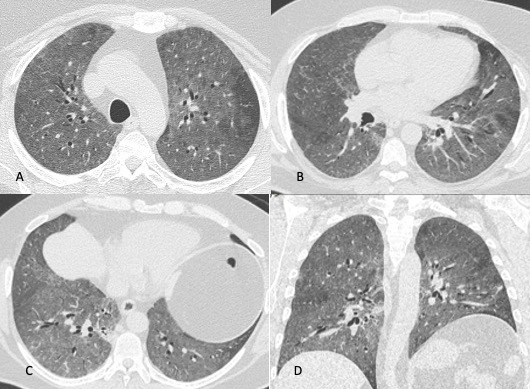

Figura 3: Uomo di 65 immunocompromesso affetto da polmonite da Citomegalovirus. Le immagini TCAR assiali (A-B-C) e la ricostruzione MPR coronale (D) mostrano il tipico pattern caratterizzato dalle presenza di "vetro smerigliato" diffuso in entrambi i polmoni con distribuzione simmetrica, si associa la presenza di alcune aree di aumentata densità con aspetto consolidativo in entrambi i lobi inferiori.

image